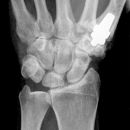

Endgelenksluxation Daumen